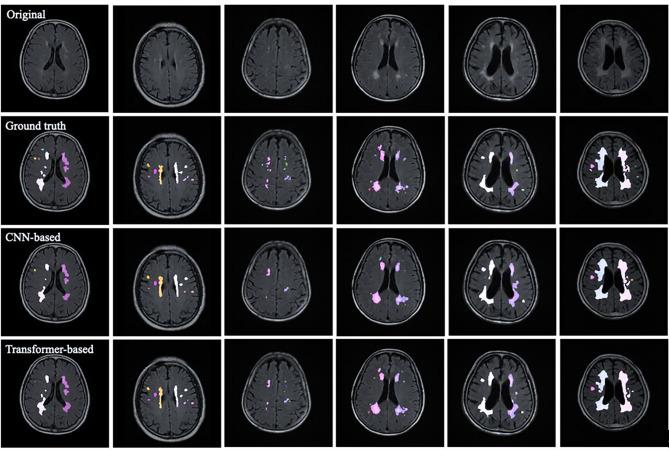

We implemented a convolution-based model (3D ResNet-50 U-Net with spatial and channel squeeze & excitation) and a Transformer-based model (3D Swin Transformer with a convolutional stem). The models were evaluated on two clinical datasets from Kaohsiung Chang Gung Memorial Hospital and National Center for High-Performance Computing. Four metrics were used for evaluation: Dice similarity coefficient, lesion segmentation, lesion F1-Score, and lesion sensitivity.

The Transformer-based model, with appropriate adjustments, outperformed the well-established convolution-based model in foreground Dice similarity coefficient, lesion F1-Score, and sensitivity, demonstrating robust segmentation accuracy. DRLoc enhanced the Transformer's performance, achieving comparable results on internal and benchmark datasets despite limited data availability.

With comparable computational overhead, a Transformer-based model can surpass a well-established convolution-based model in white matter hyperintensities segmentation on small datasets by capturing global context effectively, making them suitable for clinical applications where computational resources are constrained.